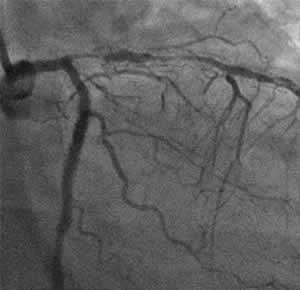

I-3 : months follow-up angio